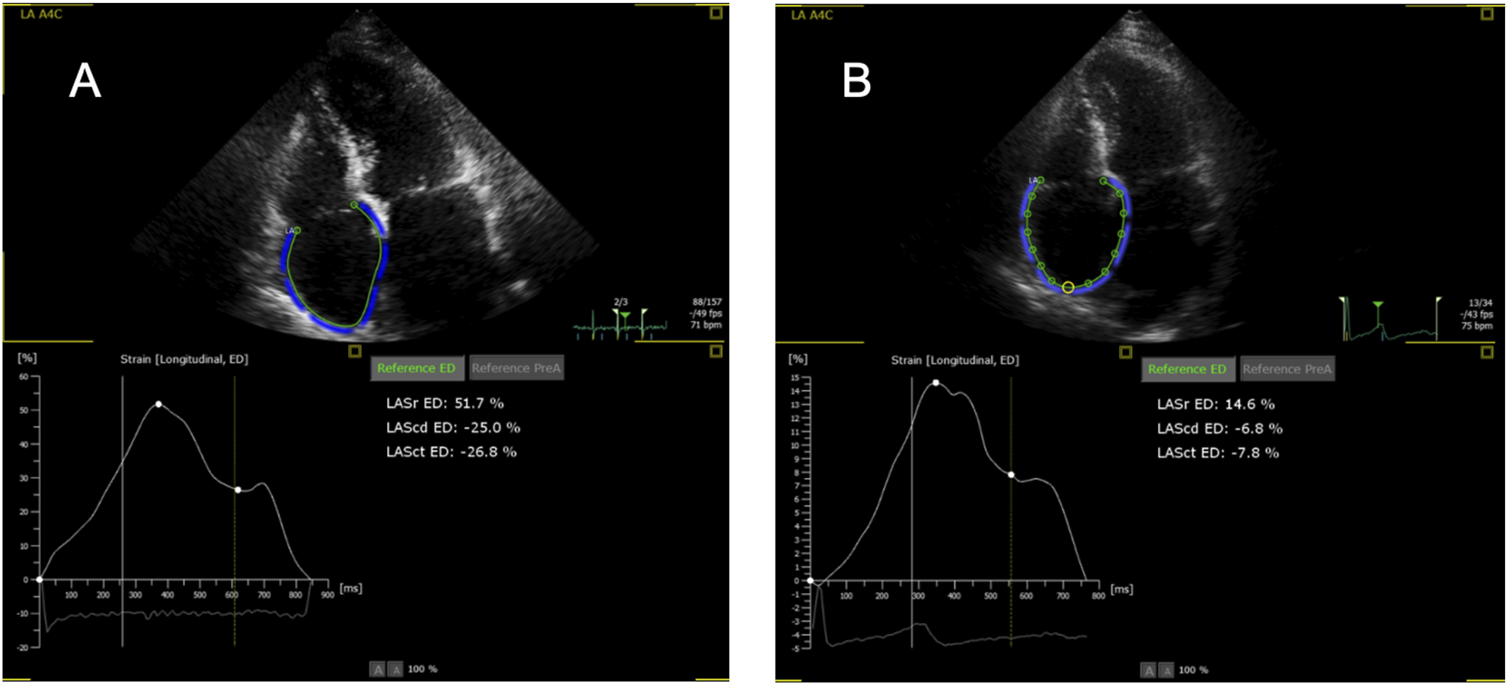

Initially, the adequacy of the automatic tracking of cardiac cycles was reviewed and corrected, if necessary. The endocardial borders of the ventricles and atria were outlined at end-diastole and end-systole in two alternative ways. The first was fully automatic (FA), without any correction by the examiner. If the FA measurement was roughly outside the anatomical boundaries, it was classified as insufficient and not used for analysis. Second, in a semi-automatic (SA) mode, with manual setting of two markers at the left and right base of the respective cardiac chamber and then automatic outlining of endocardial borders without any correction. RA measurements were conducted only via the SA mode, because the FA mode is only available for the LA; the use of LA strain software in the SA mode for measurements of RA strain is formally off-label but available by the manufacturer and used by other groups [22]. The R wave was used as a reference, and thus zero strain was set at the R wave as recommended [18]. Examples of RA measurements are shown in Figure 1.

FIGURE 1

Representative examples of right atrial strain imaging in one patient. (A) Without rejection (0R); (B) With rejection (2R). Note the wrong labeling as “LA” (left atrium), for the LA program is used for the right atrium. Sr, reservoir strain; Scd, conduit strain; Sct, contraction strain.